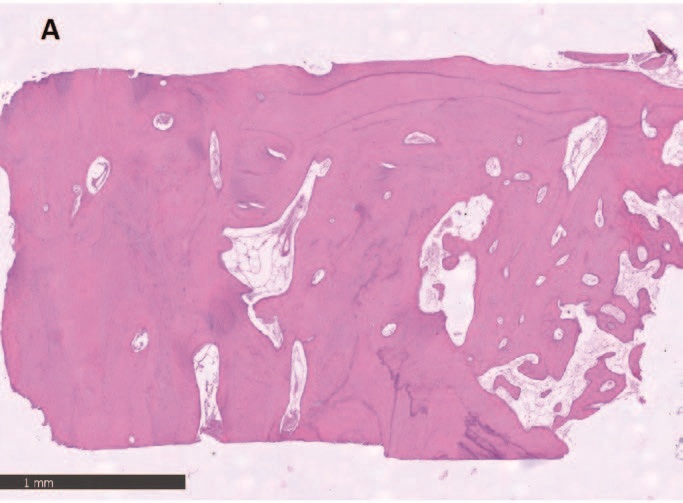

Гистологический анализ показал хорошо организованную, в основном зрелую ткань, образованную компактной пластинчатой костью с четко очерченными костными пластинками вокруг каналов Гаверсияна и Фолькмана, окруженных меньшими участками, в которых пластинки были менее организованными и богатыми остеоцитами на стадии созревания. Количество минеральной матрицы - от 69% до 72% - было особенно значительным. Воспалительного инфильтрата не наблюдалось.

Рис. 8 – Фрагмент A образца кости, взятый в 4,5, показывает широкие участки зрелой костной ткани.

Рис. 10 – Как видно, в некоторых медуллярных областях происходит отложение нового костного матрикса (синяя стрелка). Кость в пластинчатой форме свидетельствует о развитом состоянии созревания ткани.

Рис. 12 – Гистоморфометрическое исследование. Минерализованный костный матрикс занимает примерно 70% образца. Остаточный биоматериал составляет менее 2%.